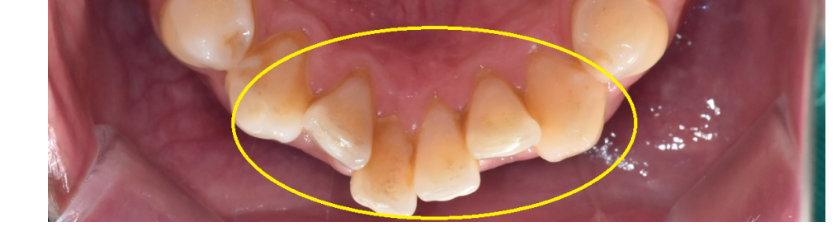

- 덧니(치열이 고르지 않음) 해결

치아가 겹쳐 있는 경우,

고르게 피게 하기 위해서는 공간이 필요하겠죠??

발치를 하지 않고도 (중요!)

치간삭제를 통해

필요한 공간을 확보하여 고른 치열을 만들 수 있답니다!!

241118 공간이 부족해서 덧니가 생겼어요ㅠㅠ